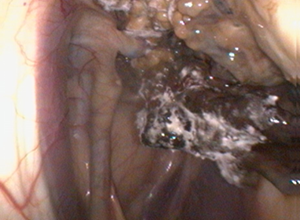

Bei dieser Erkrankung kommt es zu einer Besiedelung der Schleimhaut im Luftsack mit einem Pilzbelag. Bei den Pilzen handelt es sich um typische Pilze aus der Umgebungsluft (z.B. Aspergillen), welche also von allen Pferden ständig mit eingeatmet werden. Warum es in seltenen Fällen zur Mykose (Ansiedlung der Pilze) kommt, lässt sich nicht immer klären. Grundsätzlich ist aber davon auszugehen, dass ein geschwächtes Immunsystem (Immunsuppression) begünstigend wirkt. Das Gefährliche an dieser Erkrankung ist, dass der Pilz sich an den großen Gefäßen ansiedelt, welche durch den Luftsack hindurch verlaufen. Er ernährt sich über die Gefäßwand und führt so dazu, dass diese porös wird. Daher fallen die Pferde häufig mit wiederkehrendem Nasenbluten auf. Reißt das Gefäß vollständig auf, kommt es zu einer plötzlichen Sturzblutung, welche zum Tod des Pferdes führen kann. Daher ist es immer wichtig wiederkehrendes Nasenbluten zeitnah endoskopisch abzuklären. Weitere mögliche Symptome einer Luftsackmykose können Schluckstörungen sein, welche sich durch Probleme bei der Futteraufnahme, Futter-/Wasser- oder Speichelabfluss aus der Nase sowie Husten beim Fressen äußern können. Dies liegt daran, dass durch die Luftsäcke einige der Nerven verlaufen, welche für den Schluckakt mit verantwortlich sind und welche durch die Infektion geschädigt werden können.

Wenn die Erkrankung rechtzeitig erkannt wird, steht eine operative Behandlungsmöglichkeit zur Verfügung. Diese OP bieten wir auch bei uns in der Klinik an. Dabei werden die Gefäße verschlossen, was dank eines Gefäßkreislaufes in diesem Bereich für die Versorgung des Pferdes kein Problem darstellt. Zum einen wird dadurch das Risiko einer Blutung behoben, zum anderen stirbt der Pilz in der Folge ab, weil ihm die Versorgungsgrundlage entzogen wird. Begleitend kann der Luftsack gespült werden.